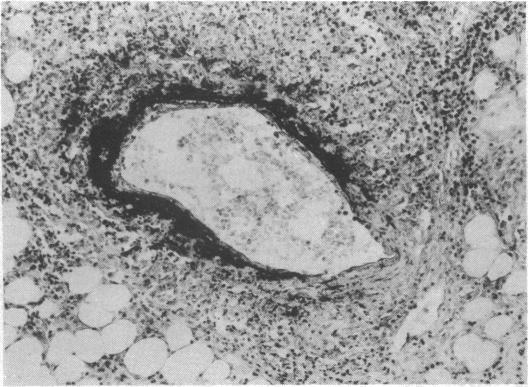

Acute abdomen in rheumatoid arthritis due to necrotizing arteritis.

Br Med J. 1973 Jun 9;2(5866):592-3. doi: 10.1136/bmj.2.5866.592.

Acute abdomen in rheumatoid arthritis due to necrotizing arteritis.类风湿关节炎所致坏死性动脉炎引起的急腹症。